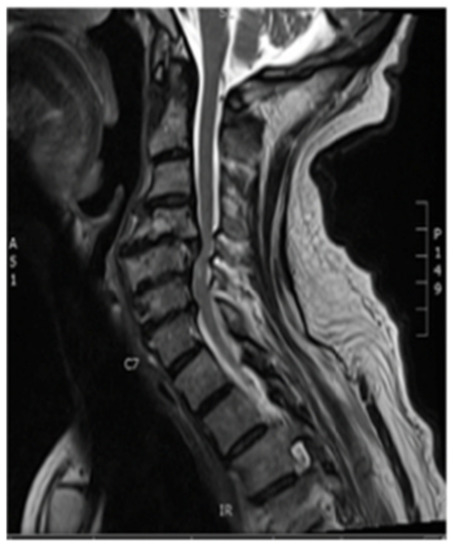

Plain X-rays revealed large anterior osteophytes most prominent from C4–C7 with severe spondylosis. MRI images show spinal cord compression from C4–C7 and myelomalacia at C5–C6, retrolisthesis at C4–C5, and severe multilevel disk degeneration (Figure 1).

Figure 1. Pre-op Sagittal Magnetic Resonance Image (MRI) (Cervical Spine).